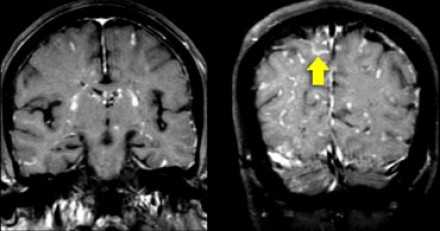

Распределение патологических участков на представленных МР-томограммах крайне напоминает рассеянный склероз . Помимо вовлечения глубокого белого вещества визуализируются юкстакортикальные очаги и даже «пальцы Доусона». В итоге было сделано заключение о саркоидозе. Саркоидоз не зря называют «великим имитатором», т. к. он превосходит даже нейросифилис по способности симулировать проявления других заболеваний.

На Т1 взвешенных томограммах с контрастным усилением препаратами гадолиния, выполненных этому же пациенту, что и в предыдущем случае, визуализируются точечные участки накопления контраста в базальных ядрах. Подобные участки наблюдаются при саркоидозе, а также могут быть обнаружены при системной красной волчанке и других васкулитах. Типичным для саркоидоза в этом случае считается лептоменингеальное контрастное усиление (желтая стрелка), которое происходит в результате гранулематозного воспаления мягкой и паутинной оболочки.

Еще одним типичным проявлением в этом же случае является линейное контрастное усиление (желтая стрелка). Оно возникает в результате воспаления вокруг пространств Вирхова-Робина, а также считается одной из форм лептоменингеального контрастного усиления. Таким образом объясняется, почему при саркоидозе патологические зоны имеют схожее распределение с рассеянным склерозом: в пространствах Вирхова-Робина проходят мелкие пенетрирующие вены, которые поражаются при РС.